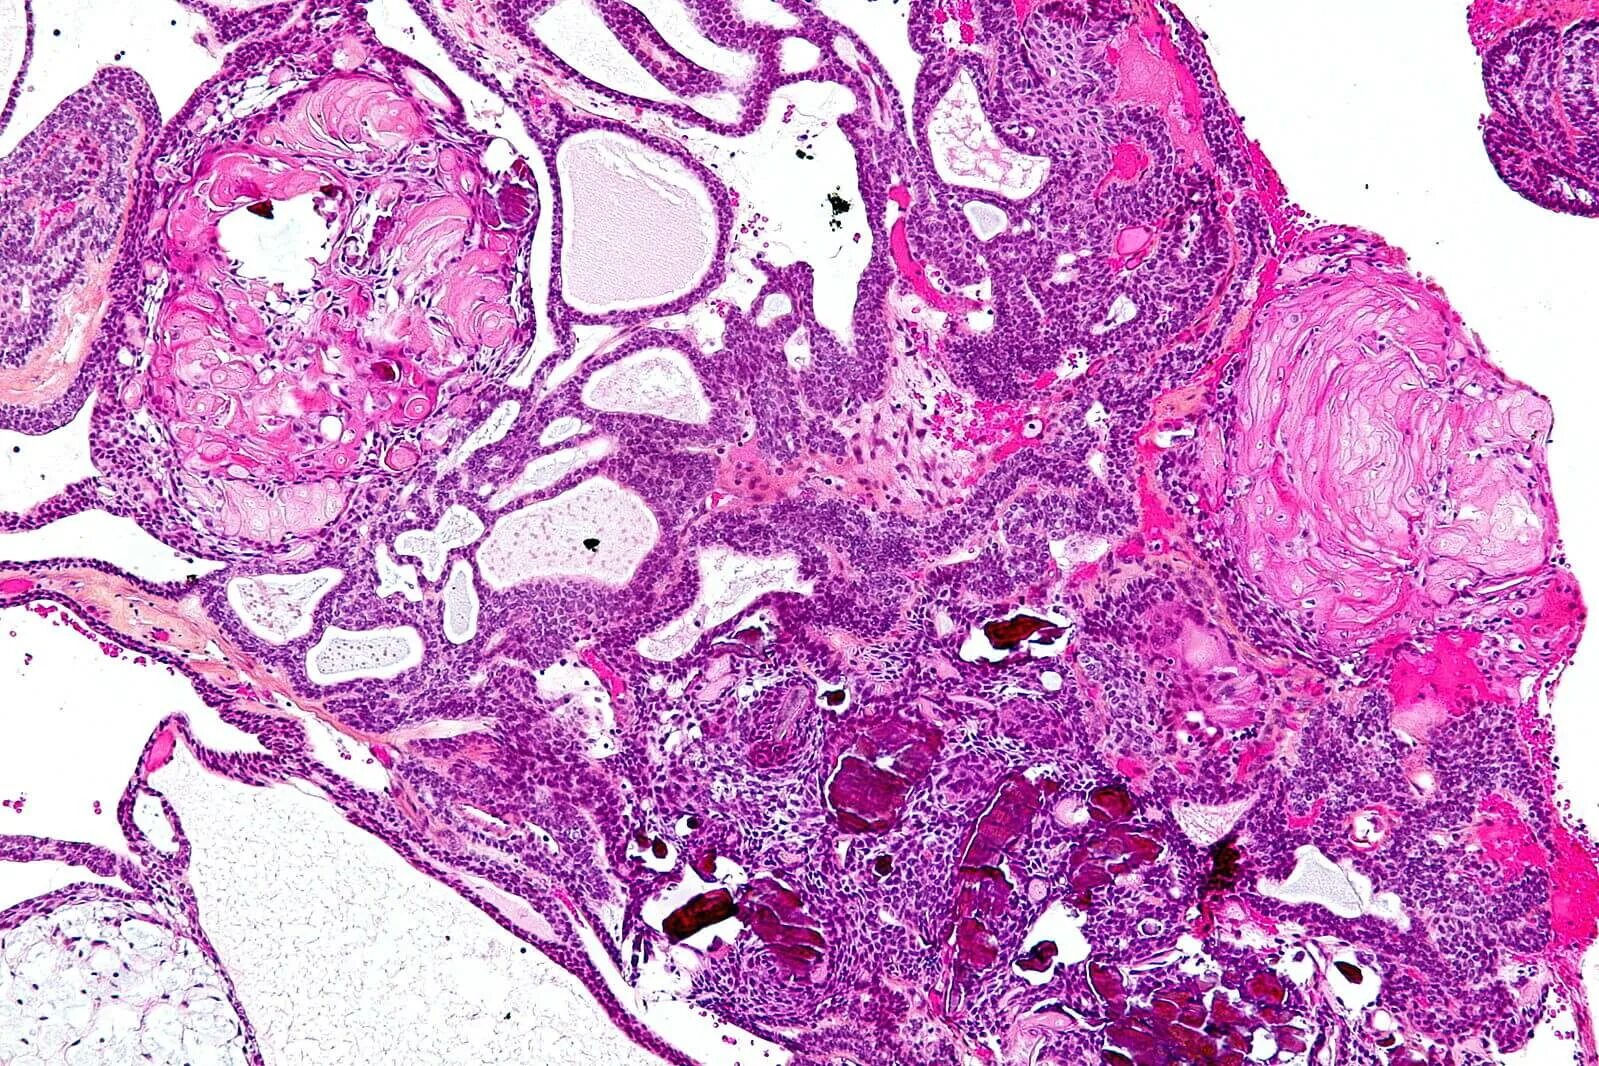

Патан пф